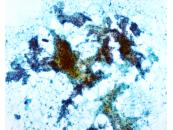

第37回日本臨床細胞学会九州連合会学会(佐賀)スライドカンファレンス症例2

種別:甲状腺

出題:○黒濱 大和 長崎大学病院病理診断科・病理部

| 年齢 | 70代 | 性別 | 女性 |

|---|---|---|---|

| 採取部位 | 甲状腺 | 採取方法 | 穿刺吸引 |

| 検体処理法 | 従来法 |

臨床所見

既往歴:甲状腺左葉良性腫瘍切除(詳細不明,35歳時)

現病歴:1週間前より頸部腫脹を自覚。頸部に軽度圧痛のある弾性硬,可動性不良の8.5x5.0cmの腫瘤を認め,画像上甲状腺右葉に石灰化を伴う腫瘍を認めた。同部より細胞診が施行された。

| 正解 | 2.乳頭癌+未分化癌 |

|---|

▼選択肢及び投票結果

| 1.乳頭癌 | 21件 | (26.2%) | |

| 2.乳頭癌+未分化癌 | 8件 | (10.0%) | |

| 3.低分化癌 | 9件 | (11.2%) | |

| 4.円柱細胞癌 | 35件 | (43.8%) | |

| 5.卵巣癌転移 | 7件 | (8.8%) | |

| 投票総数 | 80件 | (100%) |